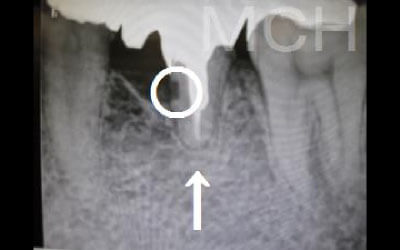

2. 顎の神経に触れるリスク

下あごの骨の中には神経が通っており、治療の際に誤って刺激する可能性があります。

しかし、事前にCT撮影を行って神経との距離を正確に把握した上で計画を立てることで、リスクは大幅に軽減できます。

さらに当院では、必要以上に骨を削らないよう専用のストッパーも併用しています。